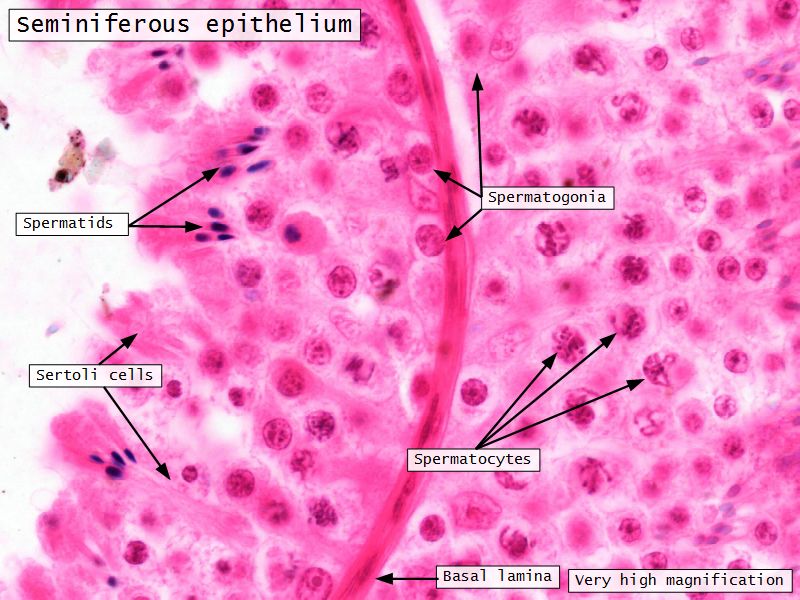

Seminiferous epithelium

- Two types of cells

- Spermatogenic cells

- Sertoli cells

Sertoli cells

- Complex columnar shape

- Basal lamina to lumen

- Irregular outline

- Envelope developing germ cells

- Large pale nucleus with indentations & large nucleolus

- Occludens junctions with adjacent cells

- Establish blood-testis barrier

Spermatogenic cells

- Several stages of spermatogenesis

- Spermatogonia

- Primary spermatocytes

- Secondary spermatocytes

- Spermatids

- Spermatozoa

Spermatogonia

- Diploid

- Sits on basal lamina

- 3 types

- Pale type A

- Small, pale nucleus

- Produce pale type A or type B

- Dark type A

- Dark nucleus

- Reserve cell to produce pale type A

- Type B

- Undergo mitosis

- Form primary spermatocytes

Spermatids

- Haploid

- Small

- Near lumen

- Condensed chromatin in nuclei

- Undergo spermiogenesis